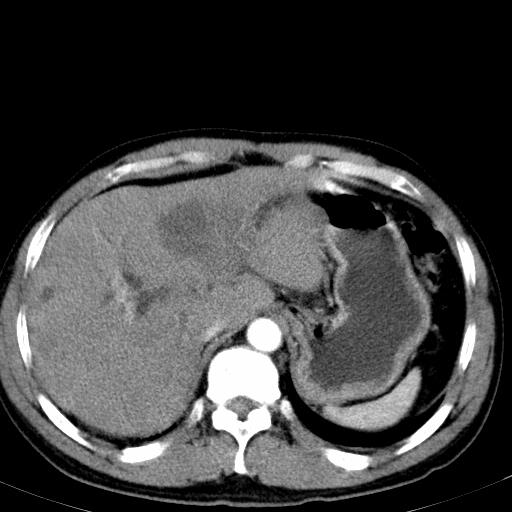

患者上腹部疼痛一月余,伴巩膜黄染;

实事求是的说,强化效果很一般,重点部位应重点观察,但有一点可以明确:肝门部胆管细胞癌。

考虑肝左叶胆管细胞癌侵犯肝门区并肝内胆管及肝总管扩张。

肝左叶肿块清度增强,所在的叶胆管扩张。考虑胆管细胞癌。